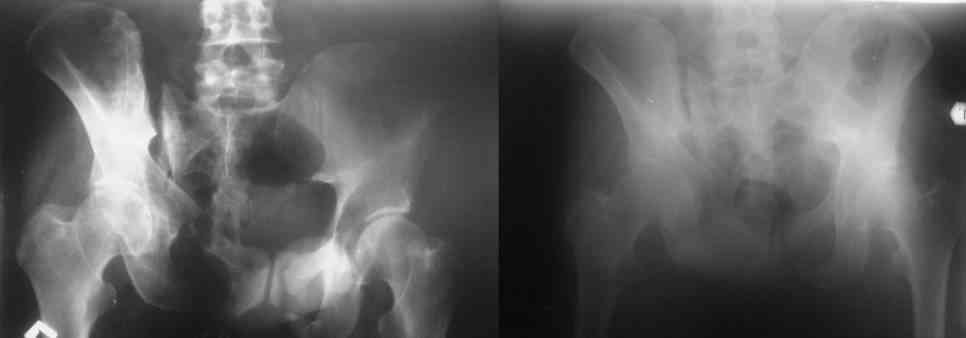

Остается только вариант закрытого аппаратного лечения. В аттаче положение отломков на вытяжении в прямой (АР) проекции. Для сравнения снимок до и во время вытяжения.